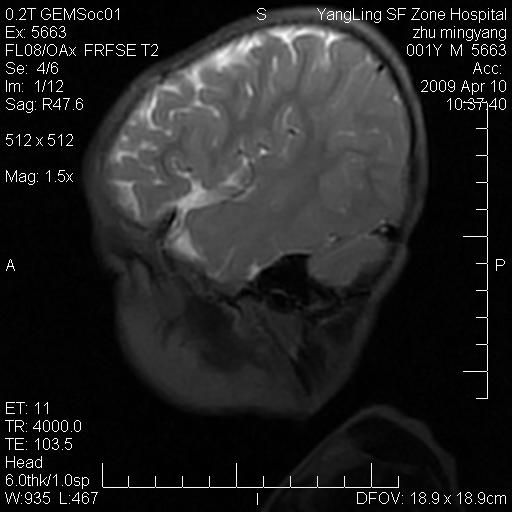

患者:1岁半,两天前外伤收住我院,ct检查小脑占位

考虑星形细胞瘤,建议增强

髓母细胞瘤或血管母细胞瘤,增强后可以鉴别;影像资料见 <。鱼博浪老师的《中枢神经系统ct与mr鉴别诊断》 小脑部肿瘤章节。

髓母细胞瘤或血管母细胞瘤!支持!

支持考虑髓母细胞瘤

考虑----髓母细胞瘤可能性大

考虑髓母细胞瘤或室管膜瘤。

支持髓母细胞瘤。

考虑髓母细胞瘤。

考虑髓母细胞瘤或星形细胞瘤

考虑髓母细胞瘤.

考虑髓母细胞瘤可能性大。

小脑肿瘤.考虑髓母细胞瘤可能.

就病灶部位及临床资料首先考虑髓母.